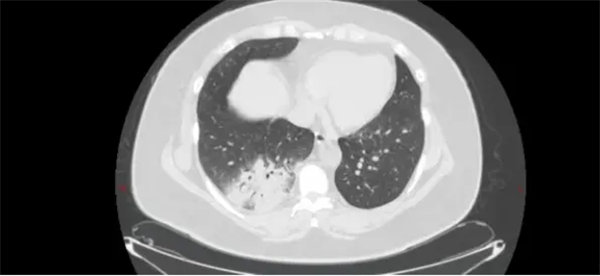

51岁的王女士(化名)持续发热5天,体温最高达39.5℃,伴全身乏力、关节肌肉酸痛。在外院输液治疗3天后仍反复发热,遂转至我院呼吸与危重症医学一科住院。主治医师李旭东接诊后,发现其胸部CT及血常规等检验结果提示非典型病原菌感染,结合患者家中养有鹦鹉的情况,高度怀疑鹦鹉热衣原体肺炎。学术主任王惠霞、科主任魏胜全与副主任医师贾汝臻综合患者长期养鹦鹉的爱好、病史、查体、CT片及相关检验结果,确认临床判断。

为进一步明确诊断,经患者及家属同意,行支气管镜肺泡灌洗并送检病原宏基因测序(NGS),结果回报支持鹦鹉热衣原体肺炎诊断。随后调整治疗方案,进行针对性精准抗感染治疗,患者很快康复出院。